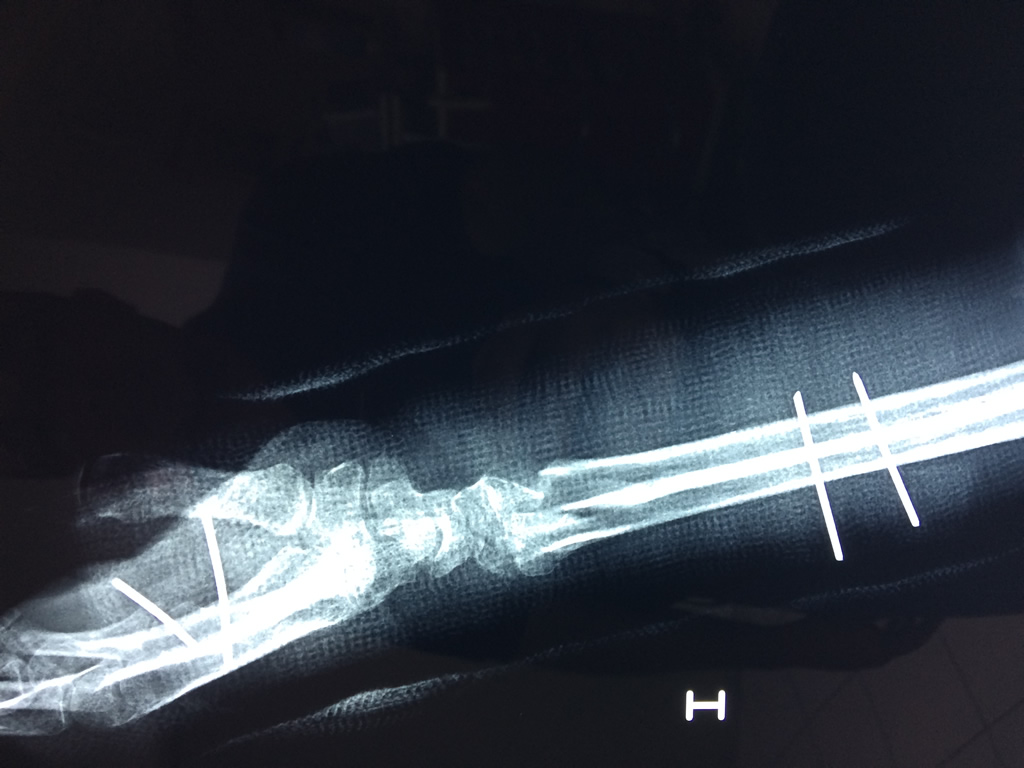

Húmero - Cirugías de Muñecas y Manos

Los procedimientos más comunes en cirugía de la mano son aquellos destinados a reparar traumatismos, incluyendo lesiones de tendones, nervios, vasos sanguíneos, y articulaciones; huesos fracturados; y quemaduras, cortes, y otros daños de la piel.